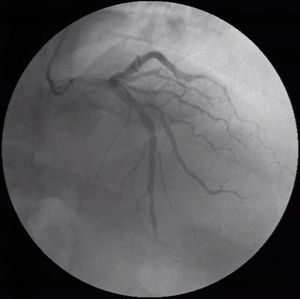

Case descriptionA 64-year-old male presented with exertional retrosternal pain. He had a past medical history of hypertension, dyslipidemia, obesity, bilateral carpal tunnel syndrome and underwent bilateral surgical release and cervical laminectomy. The resting electrocardiogram revealed an incomplete left bundle branch block, while the resting echocardiogram was completely unremarkable. He underwent a stress echocardiogram with dobutamine; at peak stress, the left ventricle developed regional wall motion abnormalities including hypokinesis of the inferior wall, associated with angina and soon followed by ventricular tachycardia, reversed with propranolol. The patient was hospitalized and underwent a coronary angiography which revealed slow flow, dominant right coronary artery with non-obstructive atherosclerosis and a left anterior descending artery (LAD) with intermediate lesions in mid and distal segments (Figures 1 and 2). A functional evaluation revealed a non-significant fractional flow reserve of 0.86 in the LAD, but a pathological CFR of 1.8 and an IMR of 61. Given the patient's symptoms, risk factors and diagnostic tests, he was considered to have microvascular angina and was treated with antiplatelet therapy, a statin, a calcium channel blocker and a transdermal nitrate, with symptomatic relief.